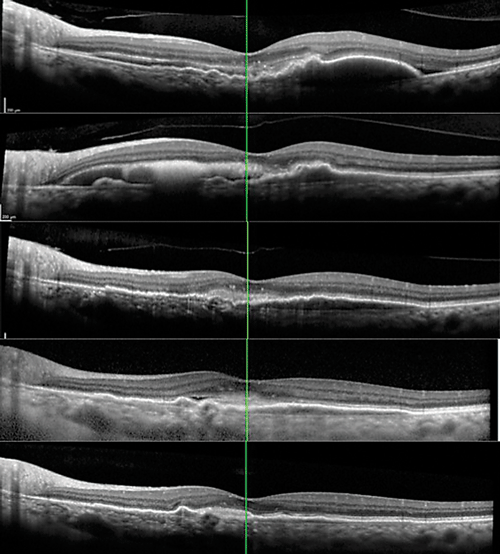

The dilated fundus examination of the right eye showed a posterior vitreous detachment and a mild epiretinal membrane. In the left eye, the dilated fundus exam was notable for large-diameter, highly elevated pigment epithelial detachments (PEDs) with adjacent subretinal hemorrhage (SRH) concentrated in the superonasal macula (Figure 1A). No drusen, geographic atrophy, or pigment mottling were present in either eye.

Fluorescein angiography with transit in the left eye showed normal transit time and vascular filling. However, there was blockage throughout the macula due to the subretinal hemorrhage. Late pooling was noted superiorly within the most temporal part of the PED. Diffuse and pinpoint leakage was also observed in the macula (Figure 1B). Optical coherence tomography of the left eye showed large serous PEDs with shallow surrounding SRH in the macula and along the superior arcade. Subretinal fluid (SRF) was also noted (Figure 1C).

| Figure 1. Color fundus photography at presentation (A) shows multiple pigment epithelial detachments (PED) associated with subretinal hemorrhage. The initial fluorescein angiogram of the left eye (B) shows blockage in the macula from the subretinal hemorrhage, late pooling within the PED in the temporal macula and diffuse and pinpoint leakage in the central macula. Optical coherence tomography (C) shows a central macular PED with adjacent subretinal hemorrhage. Raster scans through the superior macula (D) show large PEDs and small pockets of subretinal fluid. |